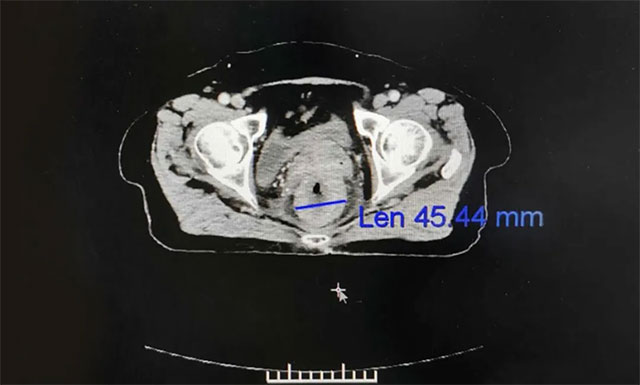

▲ 患者直肠癌再次复发,病情严重

经过复查,发现刘女士直肠局部肠壁不规则增厚,考虑仍有肿瘤活性,伴直肠周围、左髂血管旁及腹膜后大血管多发淋巴结转移,腹部造瘘术后改变,右半结肠炎性改变。之后,为求进一步放射治疗,刘女士在家人的陪伴下于7月6日慕名就诊于上海蓝十字脑科医院。

▲ 放疗后患者病灶缩小,病症逐渐缓解